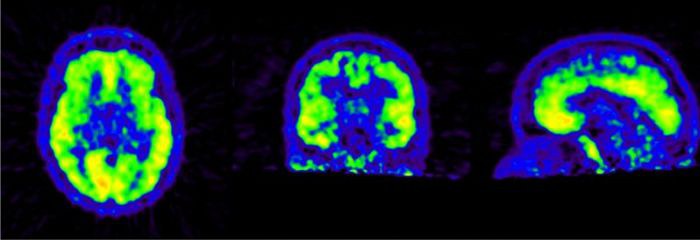

Mittels der Positronenemissionstomographie (PET) können Stoffwechselvorgänge und einzelne Moleküle, wie beispielsweise Bindungsstellen für unterschiedliche Botenstoffe im Gehirn, sichtbar gemacht werden. Hierbei sind unsere Hauptinteressen die Erforschung des Schlafs und seiner Regulationsmechanismen sowie neurodegenerative Erkrankungen (z.B. Morbus Alzheimer). Im Rahmen von Patientenstudien suchen wir dabei gesunde Personen jeden Alters zum Aufbau von Kontrollgruppen.

Im Rahmen unserer Studien führen wir eine ca. eineinhalbstündige Untersuchung des Gehirns mittels PET durch, auf welche eine ca. zehnminütige Untersuchung mittels der Magnetresonanztomographie (MRT) folgt. Je nach Studie werden anschließend unterschiedliche Zusatzuntersuchungen, wie beispielsweise Elektroenzephalographie (EEG) oder die Beantwortung von Fragebögen durchgeführt. Die Gesamtdauer der Untersuchungen beträgt etwa drei bis vier Stunden.